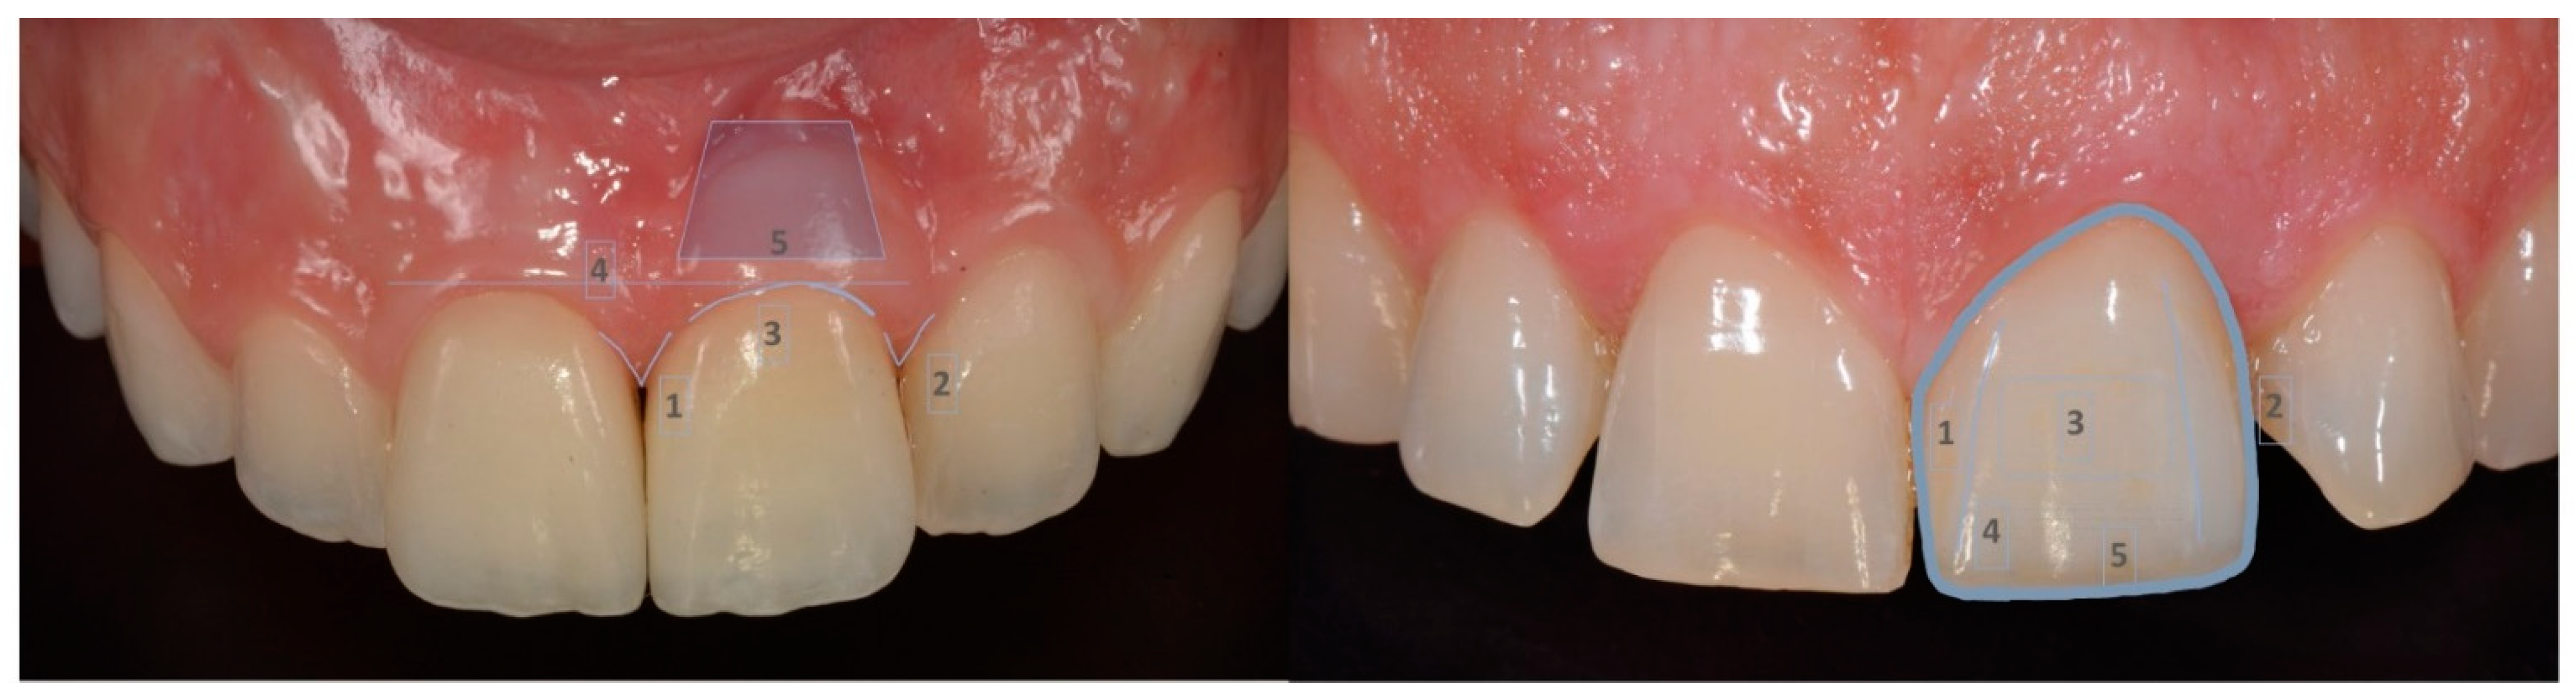

:1. Introduction

2. Materials and Methods